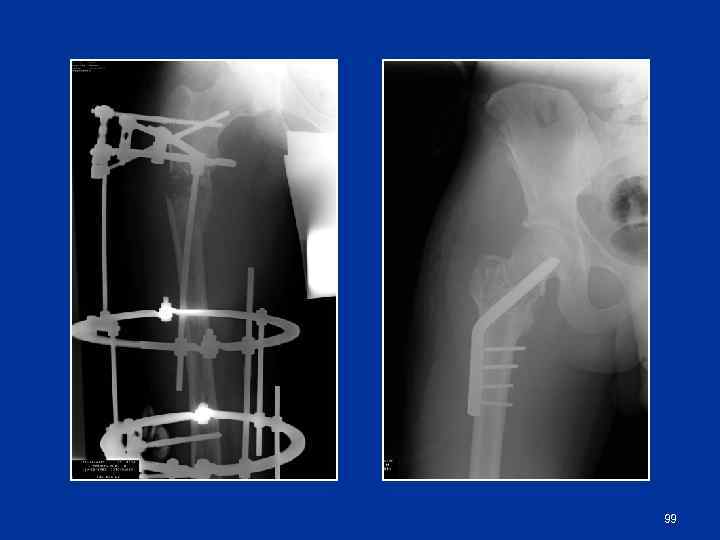

Морфологически выделяют 3 вида мозоли: эндостальная, периостальная, интермедиарная Ø Ø При полной неподвижности (металлоостеосинтез) сращение проходит 2 стадии: соединительнотканную и костную. Костная мозоль образуется между кортикальными слоями (интермедиарная костная мозоль) При значительной подвижности возникает вторичный вариант сращения в 3 стадии (соединительно-тканная, хрящевая, костная). В этом случае выражены периостальная и эндостальная костные мозоли 98

99